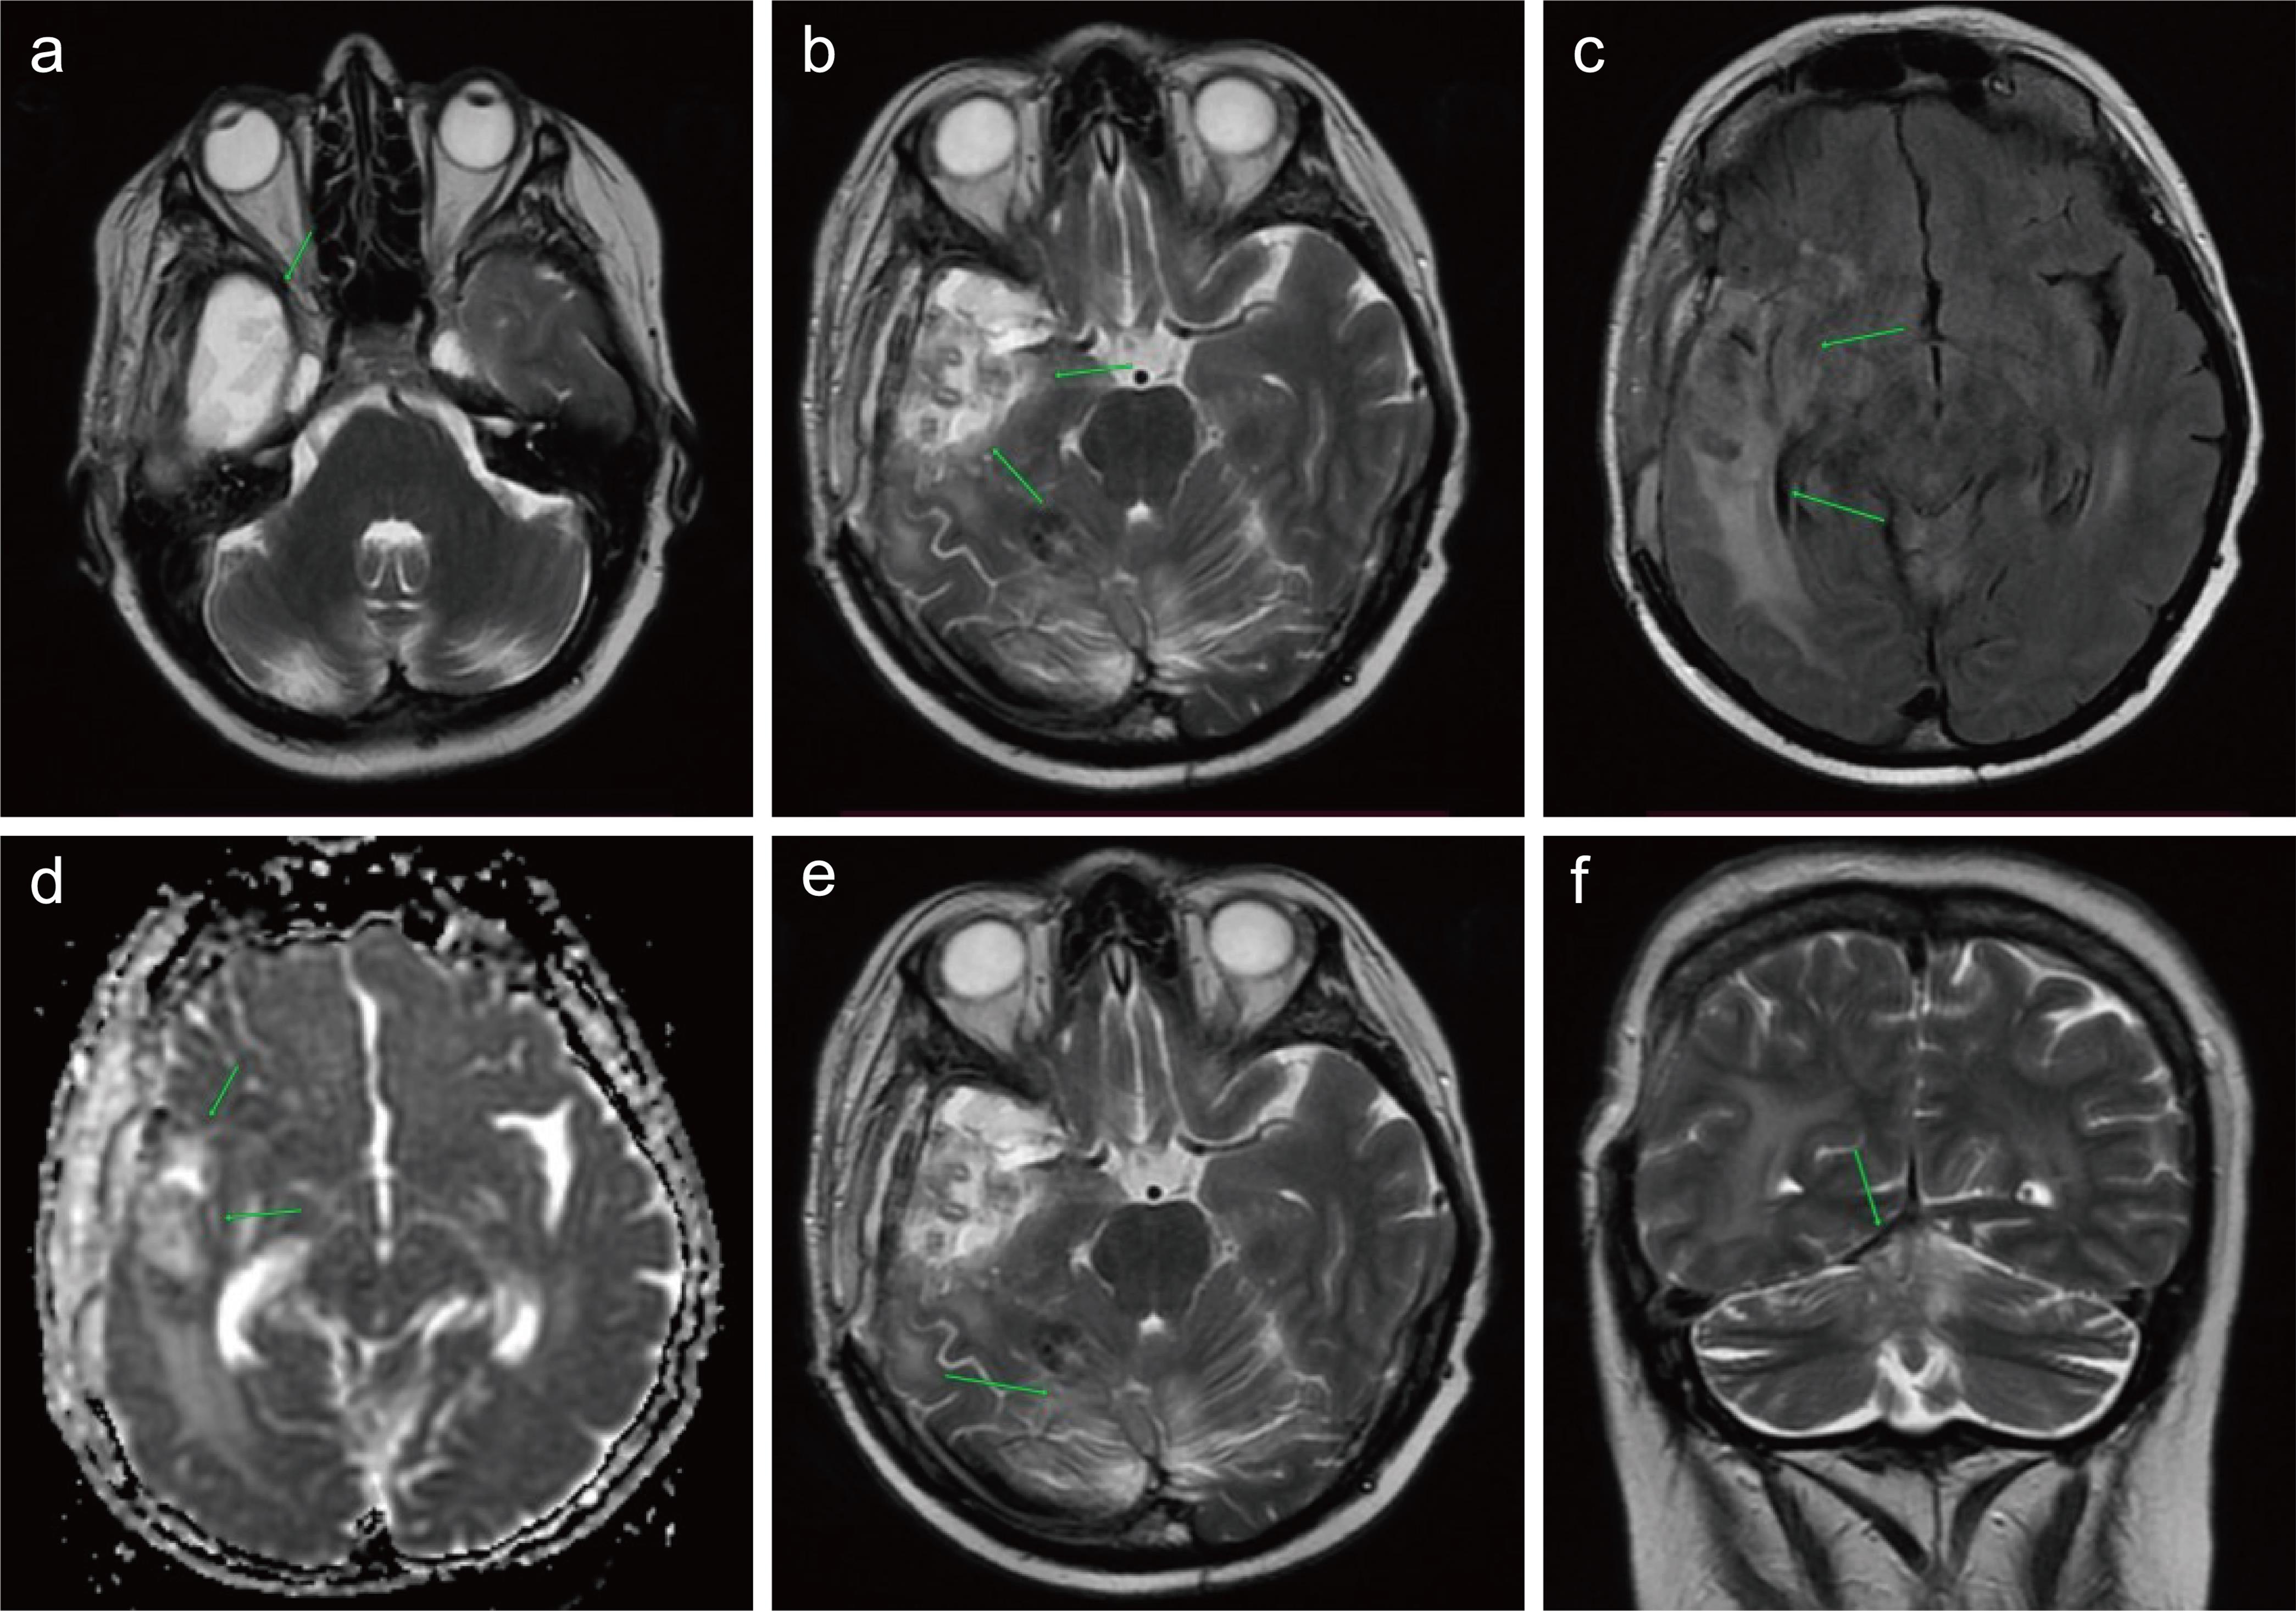

Fig. 1  Space-occupying lesion in the right temporal lobe parenchyma.

On a series of non-contrast brain computed tomography scans, a homogeneous hyperdense lesion with well-defined margins is visualized within the right temporal lobe parenchyma (a), surrounded peripherally by a hypodense zone representing brain tissue edema (February 2, 2022). There is displacement of midline structures to the left (b), along with compression and deformation of the ventricular system (c).